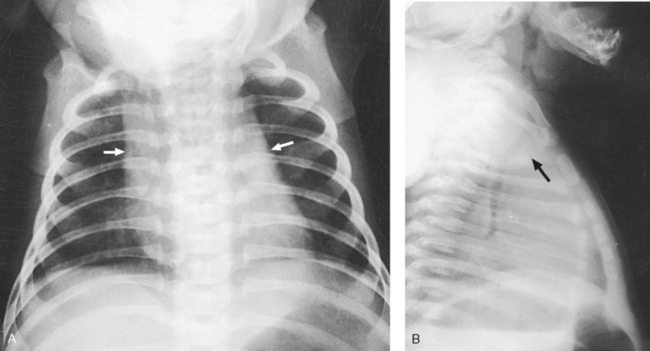

Fig. 10-8 A, PA chest radiograph showing mediastinal enlargement caused by hypertrophy of thymus (arrows). B, Lateral chest radiograph showing enlarged thymus (arrow).

In older individuals, lymphatic tissue is replaced by fat. At its maximum development, the thymus rests on the pericardium and reaches as high as the thyroid gland. When the thymus is enlarged in infants and young children, it can press on the retrothymic organs, displacing them posteriorly and causing respiratory disturbances. A radiographic examination may be made in the AP and lateral projections. For optimal image contrast, exposures should be made at the end of full inspiration.